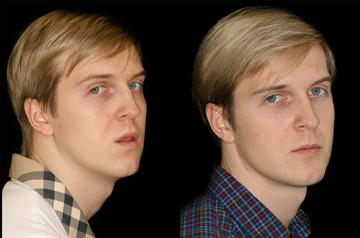

Face and Bite Correction

Primary Diagnoses

- Open bite

- Relapse after orthodontic treatment

Surgical solution

- Upper Jaw Osteotomy

- Lower Jaw Osteotomy

- Airway and Bite Correction

Surgery was performed in 2016 at our Face Smile Center by Dr. Andrey Senyuk, oral and maxillofacial surgeon.